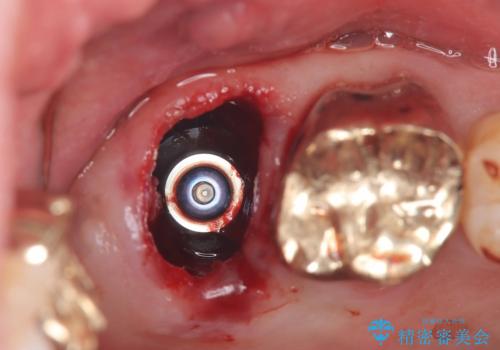

抜歯即時埋入の適応と判断し、抜歯当日にインプラント埋入を行う「抜歯即時埋入」にて処置を実施しました。

抜歯即時インプラントの利点(共振周波数解析を用いたISQ値の測定により、客観的かつ数値でインプラントの安定性を評価できるようになったため、予知性が高く安全な治療となった。)

●治療期間の短縮

抜歯とインプラント埋入を同時に行うため、抜歯窩の治癒を待つ必要がなく、全体の治療期間を短縮できる。

●低侵襲

抜歯窩を利用してインプラントを埋入するので、歯茎を切る必要が無く術後の痛みが出にくい

●骨の吸収抑制

抜歯後は速やかに歯槽骨の吸収が進むが、即時にインプラントを埋入することで骨吸収を抑制できる。